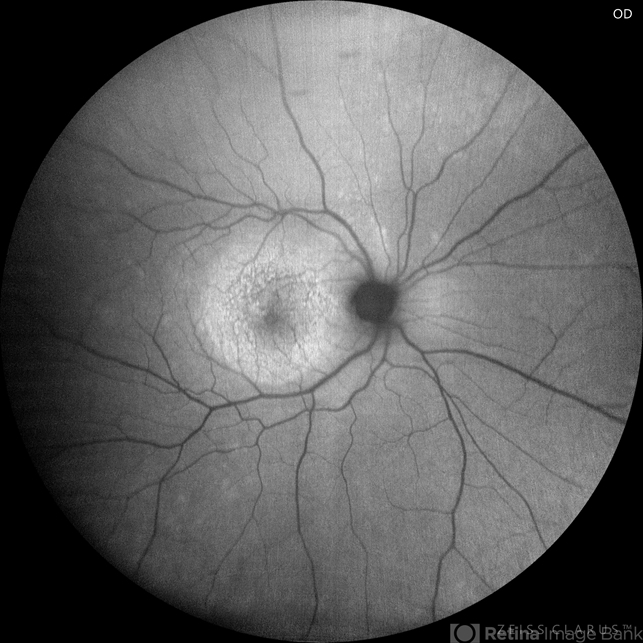

- Autofluorescence, ocular syphilis, acute posterior placoid chorioretinitis

Autofluorescence Zeiss Clarus 700 - Description

- A 36-year-old male with bilateral visual loss of 3 months' duration, with no relevant medical history on inquiry. A round-shaped lesion with well-defined borders and a yellowish-white color is observed in the macula of both eyes, accompanied by vitreous cellularity. The macular OCT shows a dentate RPE. The VDRL, FTA-ABS, and HIV tests were positive.